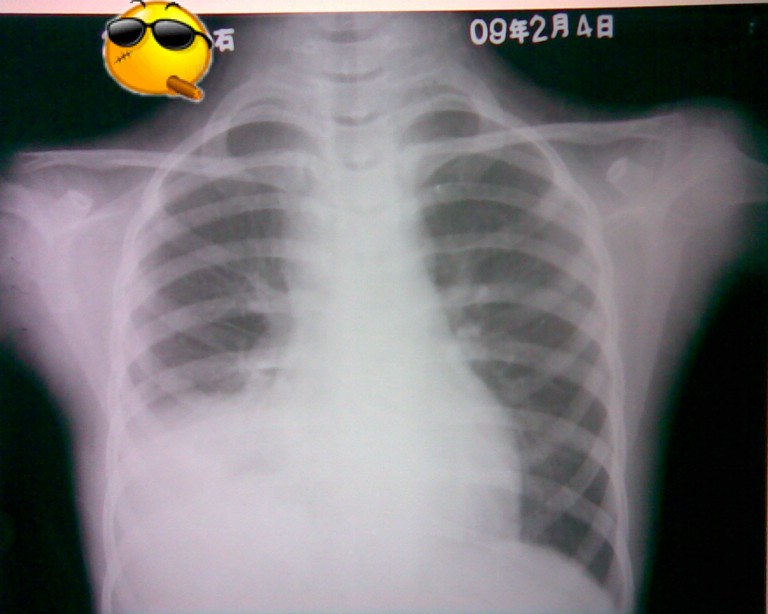

标题: PED1836:女,9岁,发热5天,听诊两肺呼吸音粗 [打印本页]

标题: PED1836:女,9岁,发热5天,听诊两肺呼吸音粗

节段性肺炎。典型!

节段性肺炎。典型!!!

节段性肺炎。片资料完整。